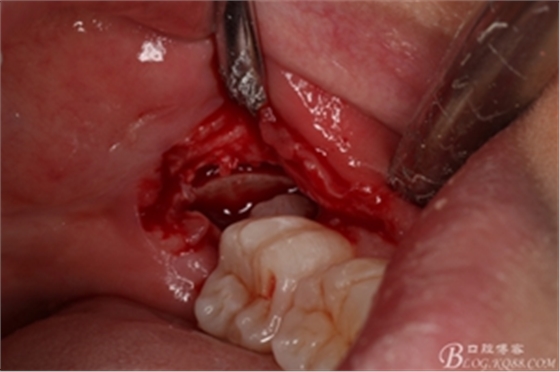

圖11.去骨---暴露出38的牙冠最大周徑

圖12.高速牙鉆分牙